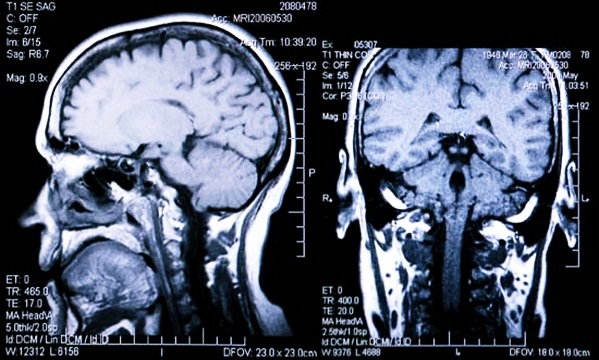

Среди неинвазивных методов выделяют ультразвуковую допплерографию и магнитно-резонансную томографию, которые позволяют оценить состояние сосудов и ликворной системы. Врачи отмечают, что хотя эти методы менее точны, они безопаснее и могут быть использованы для первичной диагностики. Важно, чтобы выбор метода основывался на клинической ситуации и состоянии пациента, что позволит обеспечить наилучшие результаты и минимизировать риски.

Измерение внутричерепного давления (ВЧД) — важная процедура, о которой много говорят в медицинских кругах. Многие пациенты и их близкие интересуются, как именно это делается и какие методы существуют. Наиболее распространённые способы включают инвазивные и неинвазивные методы. Инвазивные, такие как установка вентрикулярного катетера, позволяют получить точные данные, но требуют хирургического вмешательства. Неинвазивные методы, например, ультразвуковая допплерография, менее травматичны, но их точность может быть ниже.

- магнитно-резонансная томография (МРТ);